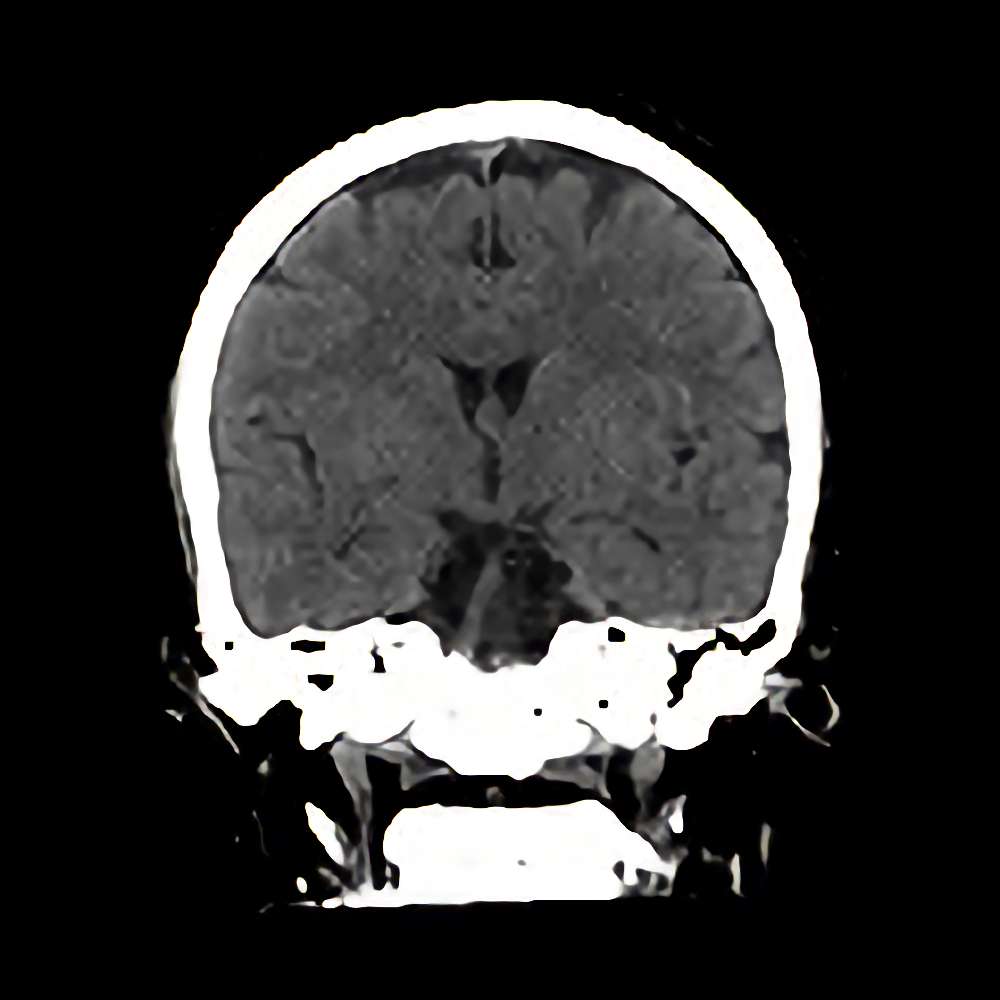

下垂体腫瘍

断層撮影

手術前1

No.’12_111 手術前1

No.’12_111 手術後